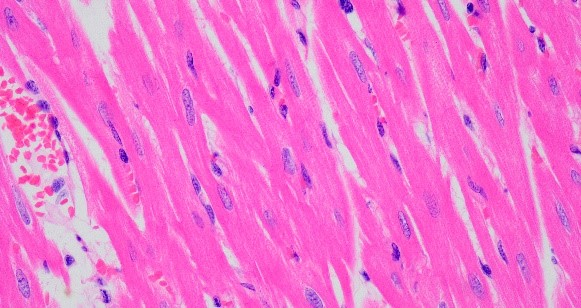

心臟環(huán)切光鏡400倍